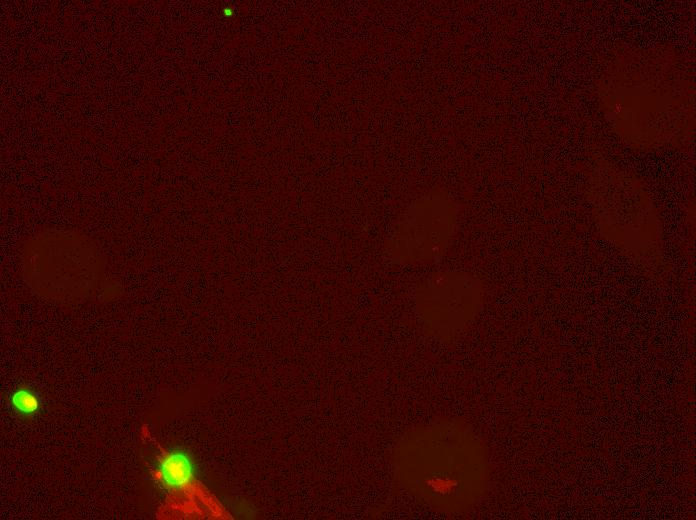

Marker sets

SMAD4

Overlay